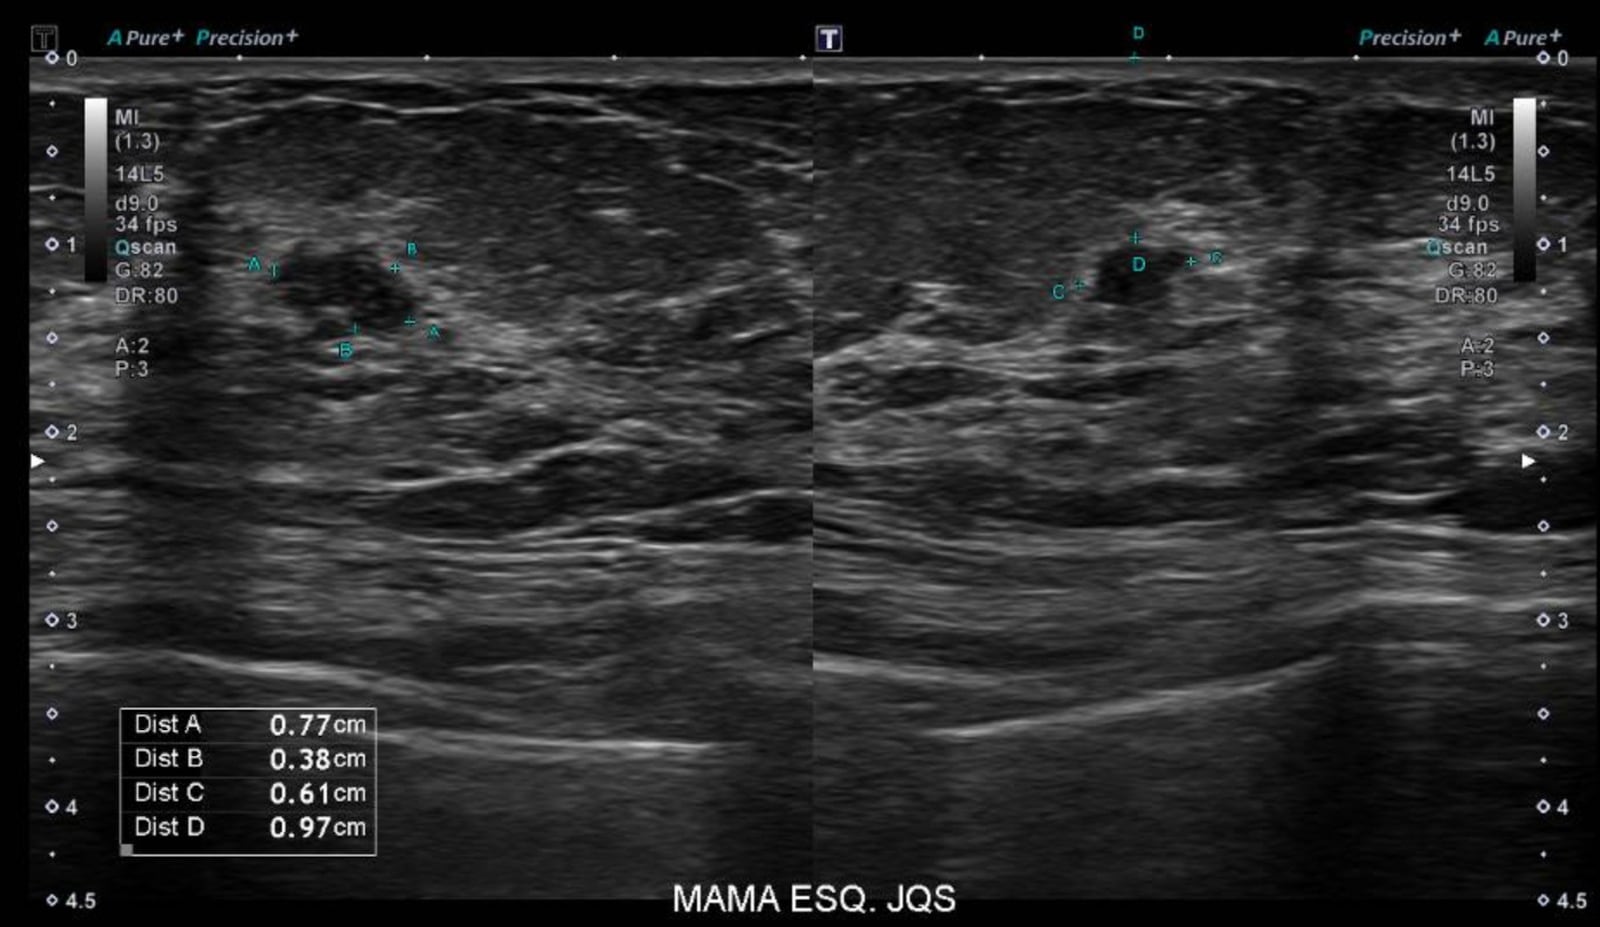

Quem cuida de toda a parte de prevenção, diagnóstico precoce, investigação de alterações benignas e acompanhamento ao longo das diferentes fases do câncer de mama na vida da mulher, é o mastologista.

A Dra. Roberta Miziara, mastologista do Hospital Moriah, explica que a mastologia é a área da medicina que realiza o cuidado integral das mamas: “O câncer é apenas uma parte do cuidado mastológico, embora seja a mais conhecida”.

Dra. Giovanna afirma que o mastologista é capaz de reconhecer alterações iniciais, muitas vezes ainda sem sintomas. Isso aumenta as chances de um diagnóstico precoce do câncer de mama, que é exatamente o que vai permitir que o tratamento seja menos agressivo e tenha maior possibilidade de cura.